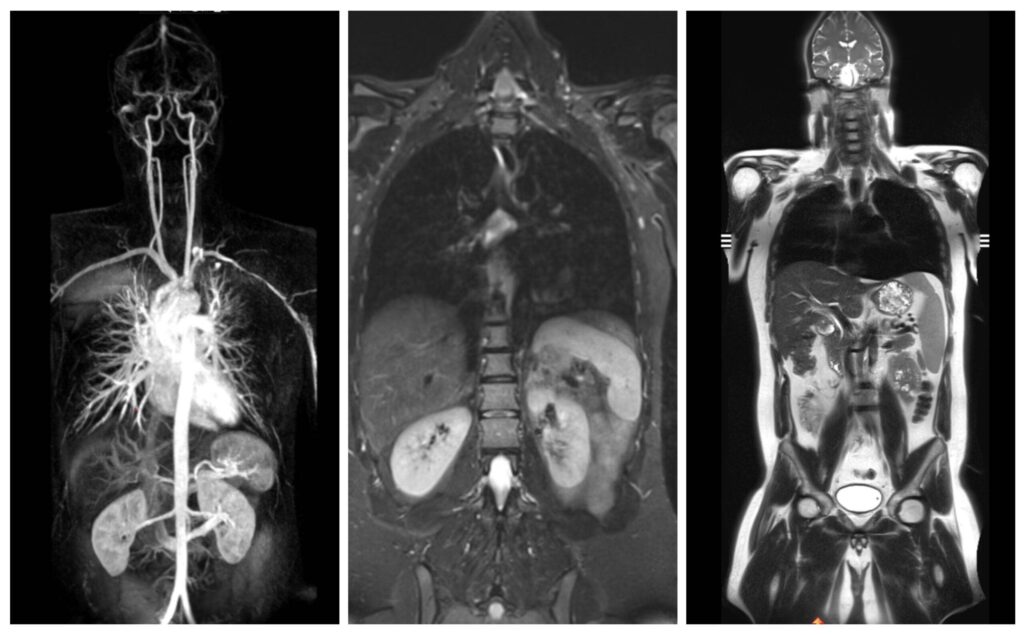

Eine Ganzkörper MRT ermöglicht es, unseren Körper – alle Organe, Gefäße, das Skelettsystem und die Gelenke, die wie Zahnräder ineinandergreifen und in ihrer Zusammenarbeit ein hochfunktionales System bilden – in seiner Ganzheit zu betrachten. Doch selbst in einem so ausgeklügelten System gibt es Schwachstellen die uns dazu veranlassen können, einen detaillierten Blick ins Körperinnere zu werfen.

Eine Ganzkörper MRT liefert hochauflösende Bilder des gesamten Körpers von Kopf bis Fuß und ist daher ideal für Vorsorgeuntersuchungen oder zur Verlaufsbeurteilung von malignen Erkrankungen:

- Eine Ganzkörper MRT kann in einer Untersuchung zur Abklärung komplexer Herz-Kreislauf-Erkrankungen herangezogen werden und gleichzeitig das gesamte Gefäßsystem sowie das Herz, die Lungen und die Bauchorgane dargestellten.

- Die Ganzkörper MRT kann auch der Früherkennung von malignen Tumorerkrankungen, beispielsweise von Bronchial- oder Nierenzellkarzinomen, im Sinne eines Screenings asymptomatischer Patienten dienen.

- Wurde bereits eine Tumorerkrankung diagnostiziert, kann die Ganzkörper MRT nützlich sein, die momentane Ausbreitung präzise zu beurteilen. Auch Fernmetastasen können durch eine Ganzkörperuntersuchung frühzeitig festgestellt werden. Die MRT ist aufgrund des höheren Weichteilkontrasts speziell in den Organen des Oberbauchs, der Lymphknoten, des Gehirns und des gesamten Skelettsystems hochpräzise bei der Erkennung von Metastasen.

Die Ganzkörper-MRT stellt eine besonders detaillierte Methode in der medizinischen Bildgebung dar, die es ermöglicht, ohne die Verwendung ionisierender Strahlung, das Innenleben unseres Körpers umfassend zu visualisieren. Mittels starker Magnetfelder und Radiowellen wird der Körper in Gänze erfasst, wodurch ein vollständiges Bild der verschiedenen Organsysteme, der Gefäße sowie der Weichteile des Bewegungsapparates wie Muskeln, Sehnen und Gelenke ermöglicht wird.

Dank der herausragenden Weichteildarstellung und der Möglichkeit, hochauflösende, detailreiche Bilder zu erzeugen, bietet die Ganzkörper MRT eine unvergleichliche Diagnostik.

Die Technologie erlaubt es, von Kopf bis Fuß ohne jegliche Strahlenbelastung detaillierte Einblicke in den menschlichen Körper zu erhalten und ist somit ideal für eine umfassende Gesundheitsüberprüfung und zur Früherkennung verschiedenster Erkrankungen geeignet. Die MRT Ganzkörper Untersuchung ist ein präzises und umfangreiches diagnostisches Bildgebungsverfahren.